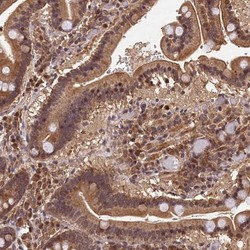

Supportive validation

- Submitted by

- Novus Biologicals (provider)

- Main image

- Experimental details

- Immunohistochemistry-Paraffin: CEP57L1 Antibody [NBP1-88761] - Staining of human duodenum shows moderate cytoplasmic and nuclear positivity in glandular cells.